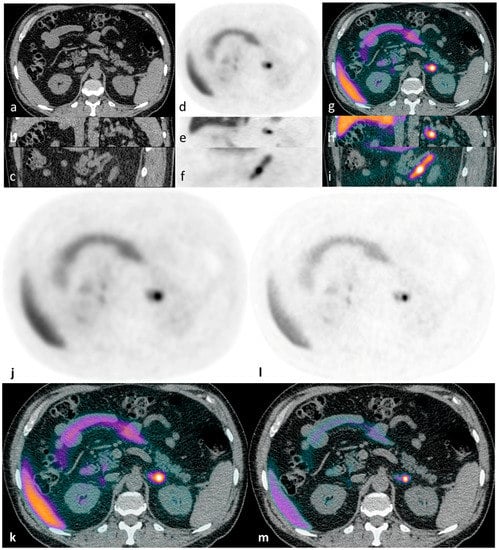

Figure 1. Illustrative case 1: A 65-year-old man with a ten-year history of hypertension and hypokalaemia, requiring multiple agents for blood pressure control (including eplerenone) and oral potassium supplementation, was diagnosed with primary aldosteronism. CT demonstrated a lipid-poor 12 mm left adrenal nodule - displayed in axial, coronal and sagittal planes (ac). 11C-metomidate PET-CT [(df) (PET) and (gi) (PET-CT)] confirmed increased tracer uptake in the left adrenal nodule. The patient underwent laparoscopic left adrenalectomy, with subsequent histology confirming a classical Conn’s adenoma. Post-operatively, he had complete resolution of his hyperaldosteronism with excellent blood pressure control on progressive down-titrating medications (currently two agents with further weaning planned), and with no requirement for supplemental potassium at four-month follow-up. For comparison, axial PET/PET-CT images are shown as reconstructed via “time-of-flight” (TOF) iterative algorithms: without (j,k) and with resolution modeling (SharpIR) (l,m).